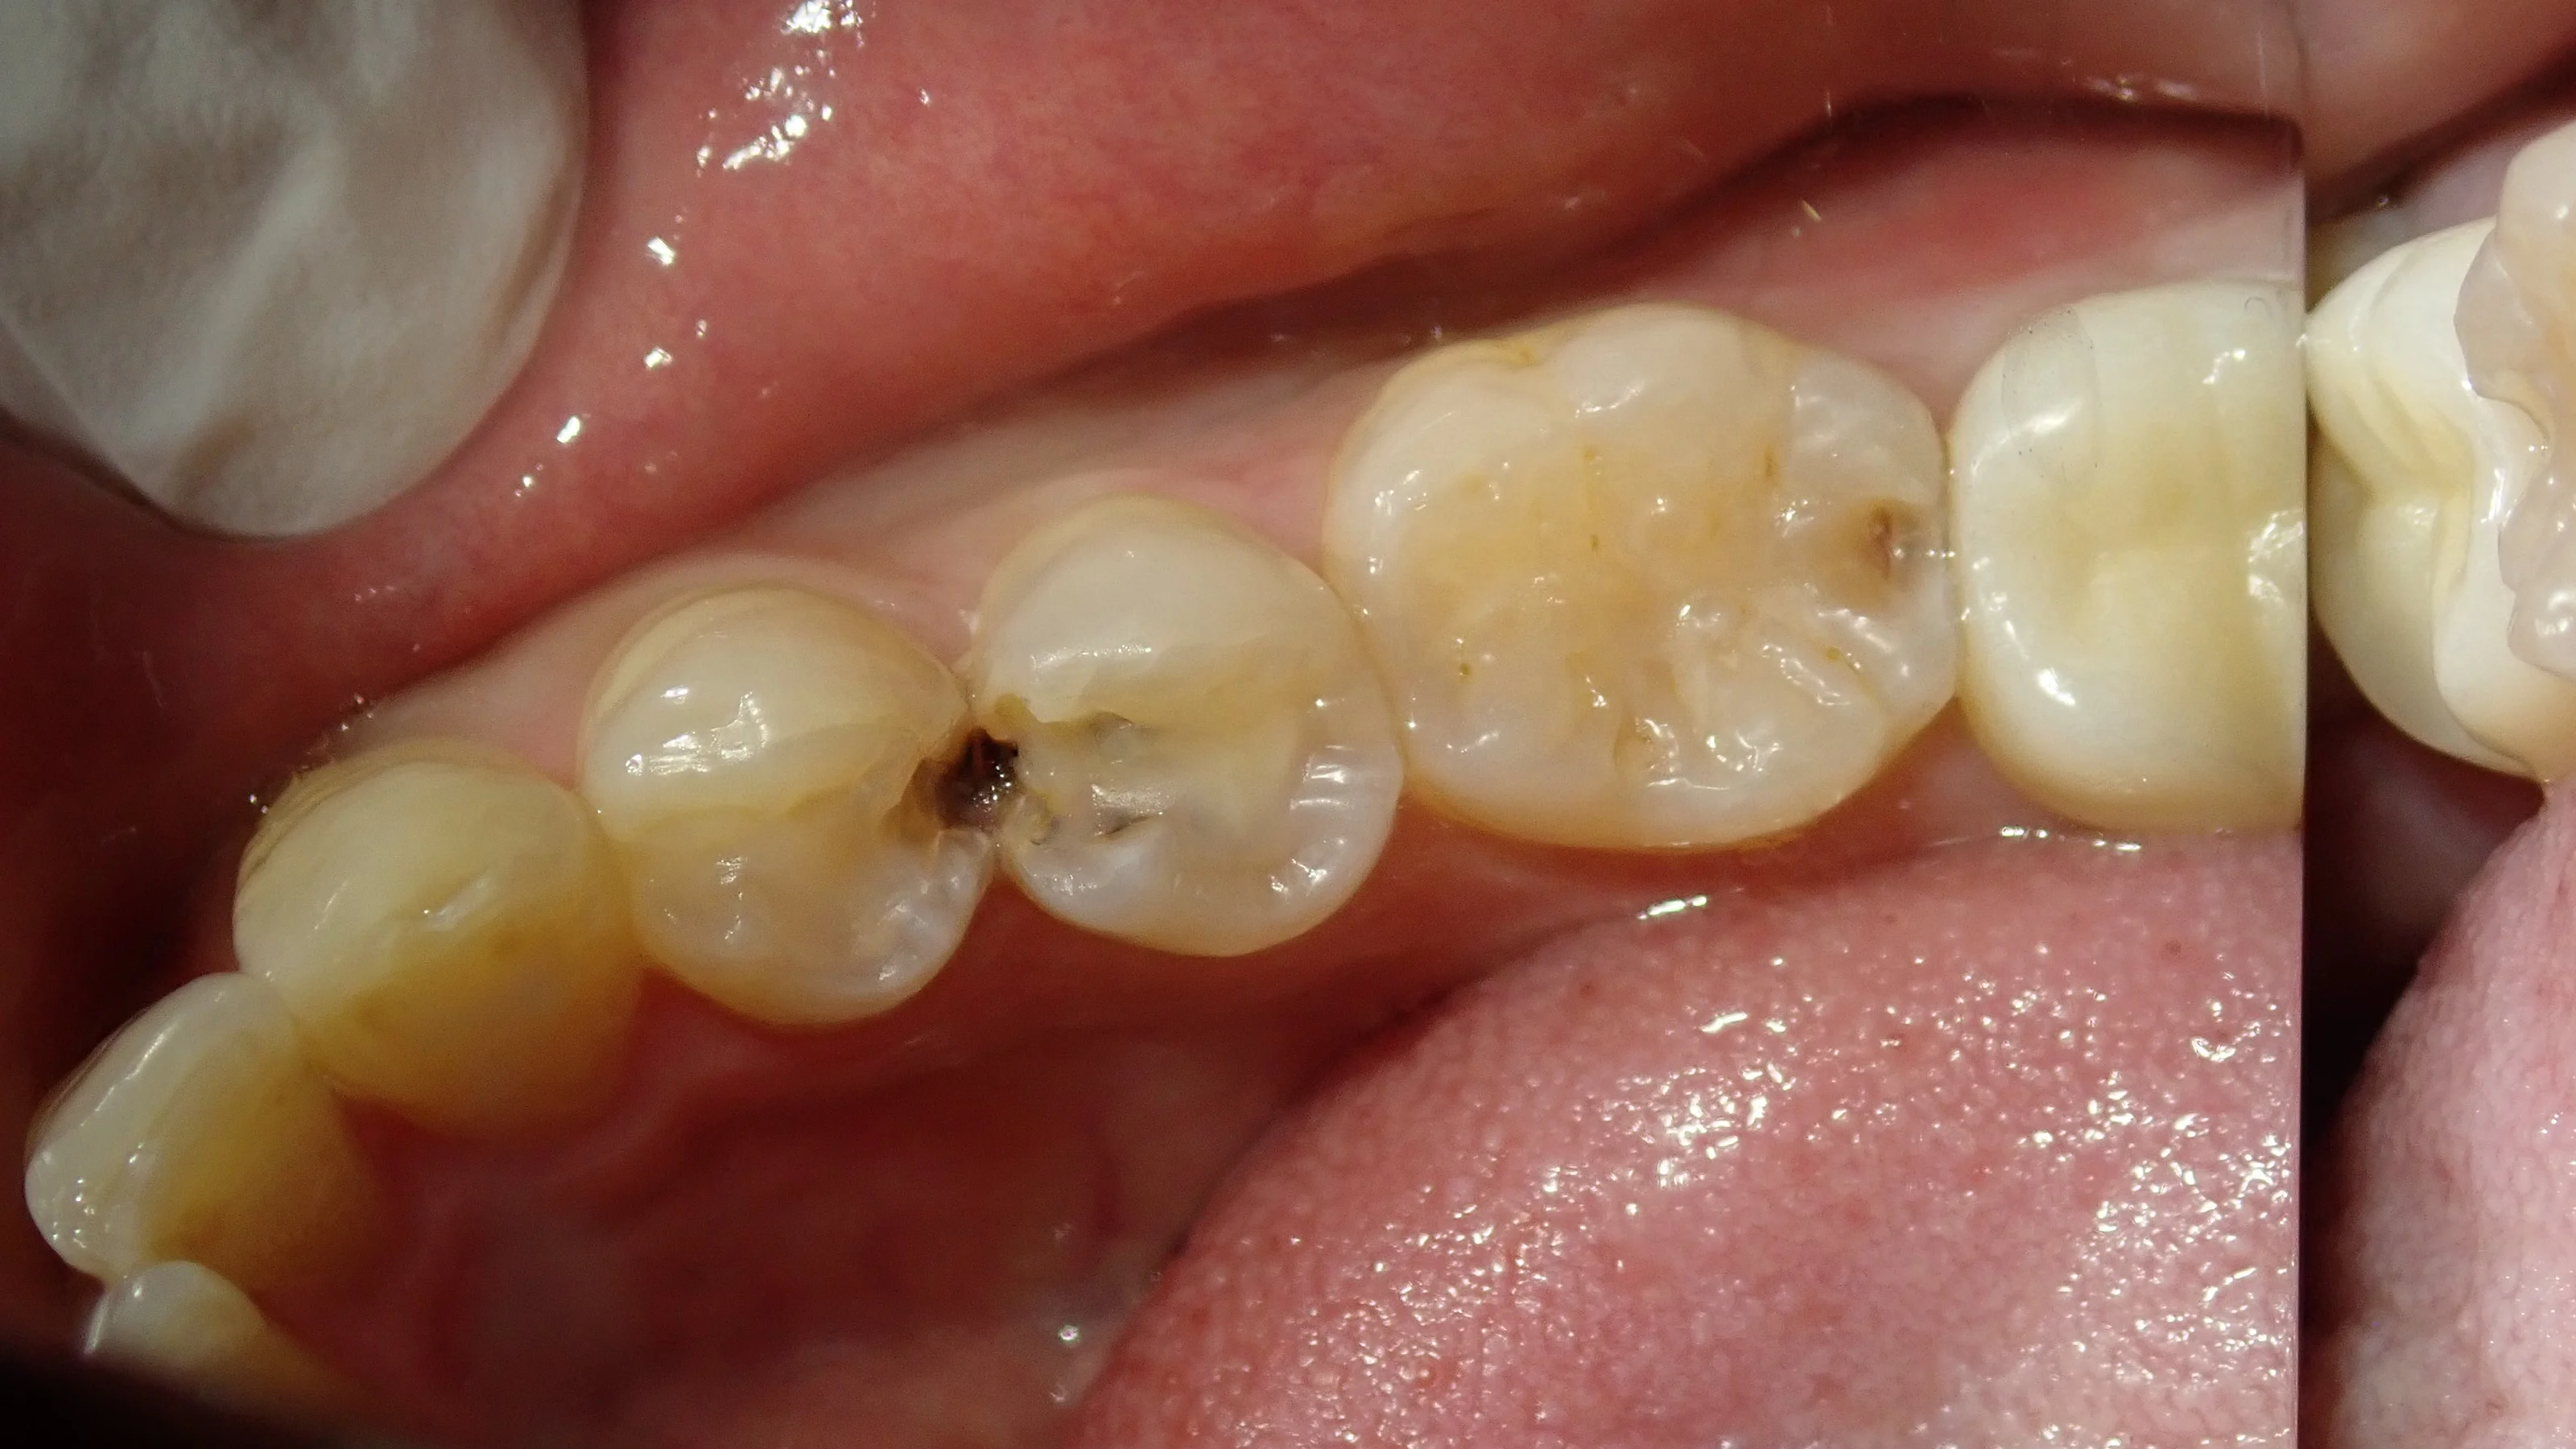

まずは、術前の状態です。

ぱっと見では分かりづらいかもしれませんが、赤丸の場所に虫歯があります。

結構大きく、深い感じですね。

非常に適合が悪い詰め物が入っているので、そのせいで磨きのこしが溜まりやすくなって、結果として虫歯になってしまったと考えられます。